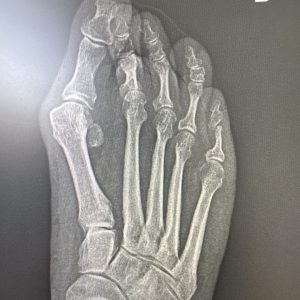

Os presento un caso de deformidad de hallux valgus intervenido con una técnica de cirugía percutánea de 3ª generación. En este ocasión, se ha realizado unas osteotomías en el primer metatarsiano y en la primera falange que se han fijado con tornillos que confiere a la corrección estabilidad, seguridad y menor dolor postoperatorio manteniendo el respeto a las partes blandas.

Los resultados radiográficos y clínicos los podéis ver en las fotos antes de la cirugía y los 3 meses de la misma.